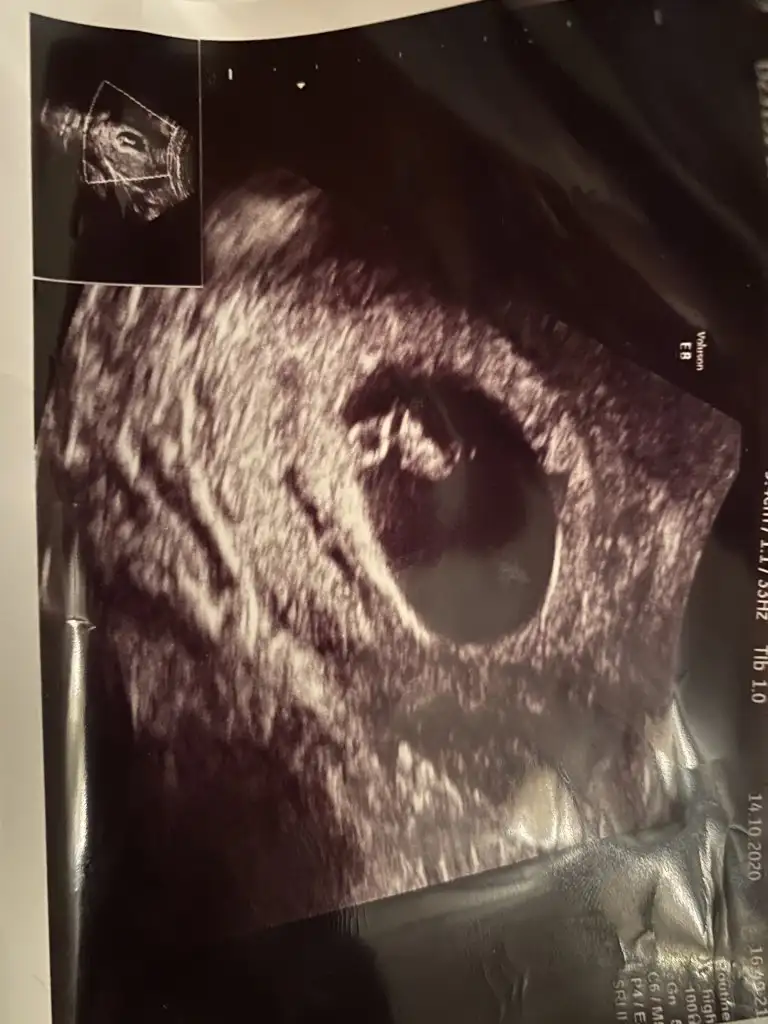

Karındansa kız vajinal ise erkek kaç haftalık burda 11 yada 12 haftada nub tahmini yaparım paylaşırsanız

Herkes sizin tahmin edebileceğinizi söylüyor lütfennnnn banada bir tahminde bulunurmusunuzz lütfennn 1. Gönderdiğim fotograf vajinal ultrason 6. Haftalarındaydı 2. Fotografta karından bakıldı 7. Haftalarındaydı hayırlısı neyse o olsun inşallahhhh ama çoooook merak ediyorum dört gözle cevabınızı bekliyorumLÜTFENNNNN